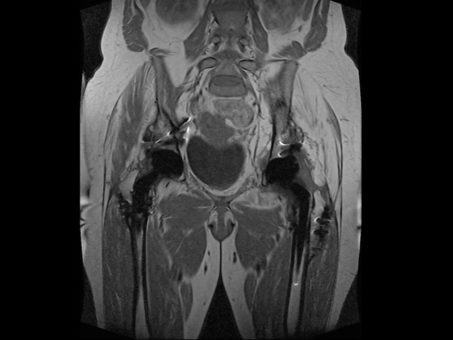

Данная диагностика позволяет изучать необходимые топографические данные, а также структуры многих тканей и органов, которые расположены в районе нахождения таза.

Метод определяет проблемы в окружающих тканях и костях и сосудах: крестец, лимфоузлы, капилляры, кости таза. За счёт хорошей визуализации, которую даёт магнитно резонансная томография, можно производить диагностирование раковых заболеваний половых органов.

У женщин определить многими другими способами патологию бывает нелегко из-за особенностей анатомии. Но МРТ, за счёт создания послойных срезов (в компьютере), выявляет на ранних сроках расположение образования, его размеры и структуру. Так можно предупредить развитие болезни.